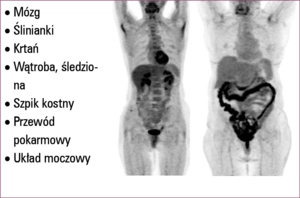

PET jest badaniem czynnościowym, umożliwia ocenę określonej funkcji komórki, dlatego od pytania postawionego przez onkologa zależy przebieg badania i wybór odpowiedniego radiofarmaceutyku.

Badanie PET jest obecnie jednym z ważniejszych narzędzi stosowanych w diagnostyce schorzeń onkologicznych. Badanie to jest symbolem nowoczesnej diagnostyki onkologicznej. Metoda polega na podaniu choremu odpowiedniej substancji chemicznej wyznakowanej emiterem promieniowania pozytonowego, biorącej udział w określonym procesie biologicznym. Pozyton, w bliskim sąsiedztwie miejsca emisji, ulega interakcji z elektronem (anihilacji). W wyniku tej reakcji powstaje promieniowanie gamma monitorowane przez aparat. Ponieważ w wyniku anihilacji powstają dwa promienie gamma biegnące w dwóch przeciwnych kierunkach, w rejestracji wykorzystuje się zjawisko koincydencji: dane zdarzenie jest rejestrowane, jeśli dwa przeciwlegle leżące detektory zostaną pobudzone w tym samym czasie. Dzięki temu uzyskiwane obrazy charakteryzują się znacznie lepszą rozdzielczością. Możliwe jest znaczne ograniczenie promieniowania rozproszonego w eń onkologicznych. Badanie to jest symbolem nowoczesnej diagnostyki onkologicznej. Metoda polega na podaniu choremu odpowiedniej substancji chemicznej wyznakowanej emiterem promieniowania pozytonowego, biorącej udział w określonym procesie biologicznym. Pozyton, w bliskim sąsiedztwie miejsca emisji, ulega interakcji z elektronem (anihilacji). W wyniku tej reakcji powstaje promieniowanie gamma monitorowane przez aparat. Ponieważ w wyniku anihilacji powstają dwa promienie gamma biegnące w dwóch przeciwnych kierunkach, w rejestracji wykorzystuje się zjawisko koincydencji: dane zdarzenie jest rejestrowane, jeśli dwa przeciwlegle leżące detektory zostaną pobudzone w tym samym czasie. Dzięki temu uzyskiwane obrazy charakteryzują się znacznie lepszą rozdzielczością. Możliwe jest znaczne ograniczenie promieniowania rozproszonego w tworzeniu ostatecznego obrazu scyntygraficznego.

Kamieniem milowym w rozwoju tej metody było wprowadzenie urządzeń hybrydowych. Obecnie praktycznie wszystkie dostępne skanery pozytonowej tomografii emisyjnej są urządzeniami hybrydowymi – PET/CT. Aparat składa się z wielorzędowego tomografu TK i gamma kamery PET. TK spełnia dwie podstawowe funkcje:

1. Pozwala na uzyskanie obrazu morfologicznego ciała badanego, na który nakładany jest obraz scyntygraficzny (fuzja obrazów). Dzięki temu możliwa jest dokładniejsza lokalizacja obszarów zwiększonego gromadzenia znacznika.

2. Badanie TK jest odzwierciedleniem gęstości tkanek, od której zależy pochłanianie promieniowania gamma. Dzięki danym uzyskanym na podstawie TK możliwe jest wprowadzenie korekcji pochłaniania promieniowania gamma powstającego w wyniku anihilacji. Bez zastosowania tego typu korekcji jakość badania byłaby niewystarczająca. Rozdzielczość aparatów PET wynosi około 3-4 mm.